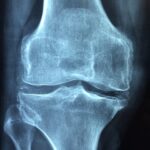

💪 Bones Are Not Built by Calcium Alone

Most people grow up hearing one word for bone health: calcium. But strong bones don’t happen in isolation. Your body needs allies — magnesium, phosphorus, vitamin D, and alkaline support — to actually utilize calcium. Here’s the deal: one pinch of slaked lime contains bioavailable calcium and acts as an alkalizing agent in your meal. It’s like a silent code that unlocks the full potential of your nutrients.

Slaked lime, also known as calcium hydroxide, when used sparingly and responsibly, can align with your natural chemistry to rebuild bone density. Just a pinch. Not more. Not less.